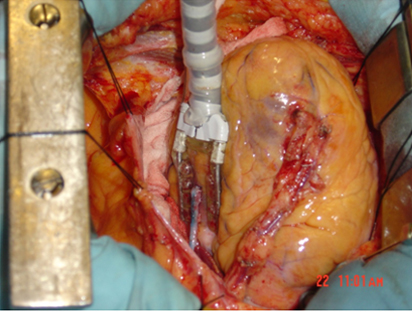

Sometimes we have to remove calcified thickened tube like material from within the Artery Called PLAQUES. This procedure is called ENDARTERECTOMY

Endarterectomy Specimen